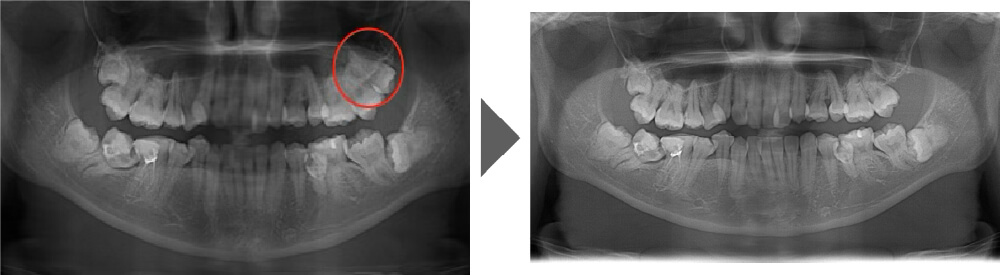

抜歯症例②

しっかり生えており、非常に磨きづらく虫歯のリスクの高い歯です。 上を2本とも抜歯しました。

【抜歯所要予約時間】

各15分

(麻酔の時間があるので処置自体はもっと短いです)